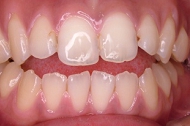

CASE2

↓前歯の歯並びを きれいに治したい。

(35歳/女性)

|||||||||

概要・担当医コメント:叢生・審美障害↑

動的治療期間13ヶ月(12回)/非抜歯/費用概算:55万円

上は固定式のブラケット矯正で,下は患者様ご自身が着脱するマウスピース矯正の治療を行いました.治療結果には大変満足されているそうです.